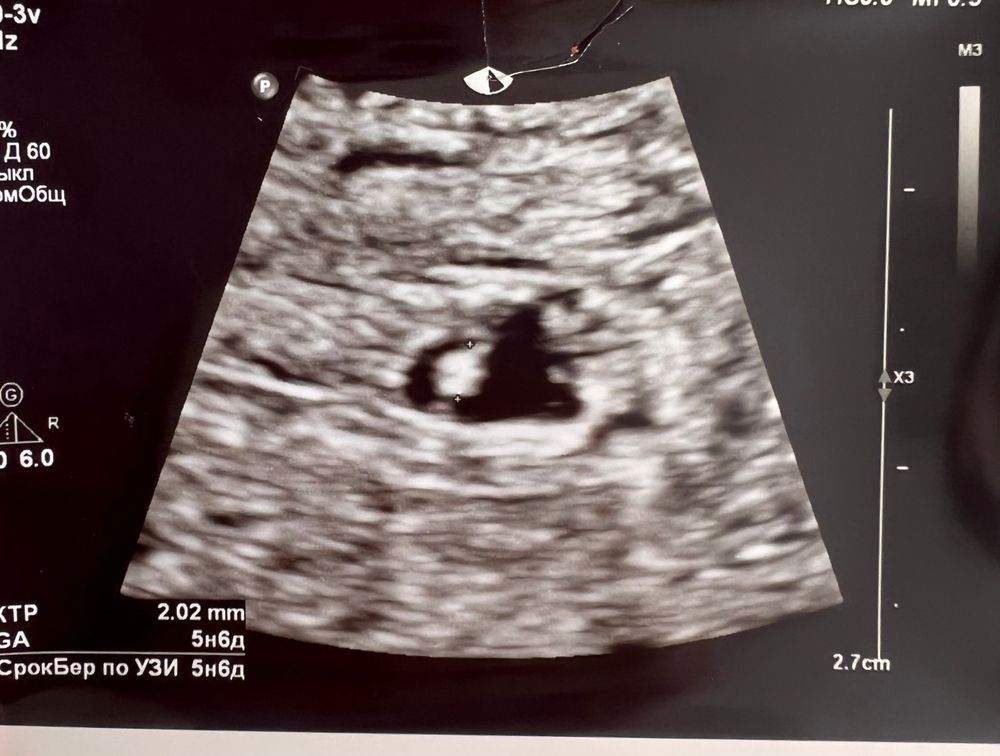

Мало места эмбриону в ПЯ?

В прошлую беременность так было. Разница между пя и эмбрионом в неделю. Спросила у врача, почему так, она только плечами пожала и сказала через 2 недели на контроль прийти. Я пошла раньше, потому что почувствовала, что что-то не то, а по УЗИ уже и эмбриона в матке не было, и пя, процесс разложения уже начался и плюсом подозрение на пузырный занос. В эту беременность на первом узи пя на 4,3, эмбрион на 5,5. Контроль через 10 дней и через 10 дней все было уже нормально, пя и эмбрион сроку соответствуют. Только ждать и верить, все может быть

Надеюсь у кого-то была такая история с хорошим исходом. Но у меня нет. В сентябре была Бер, пя росло медленно, ХГЧ тоже, ктр соответствовал сроку. Надеялась и верила до 7 нед.

Елена, у меня в дневнике есть запись. Можете почитать. Но у меня разница в 3 мм была. Может ещё у вас разгонится

Елена, сожалею, что все так вышло 😞надеюсь в скором времени все получится 🙌🏽! У меня сейчас такая же разница между эмбрионом и ПЯ

Елена, у вас была разница 3 мм, потом разогнались?